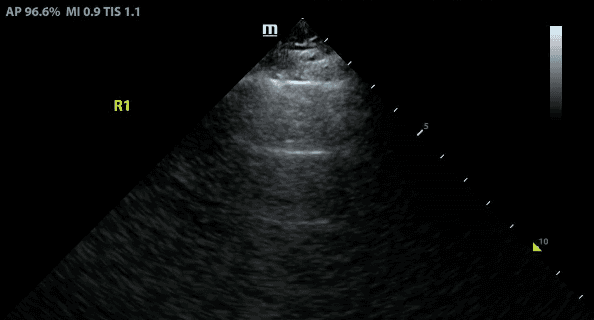

A lines are hyperechoic (ie. bright) horizontal lines that occur equidistant from the pleural line.

A lines are created by repetitive reflections between the pleural line and the ultrasound probe.

A lines are best seen when the transducer is positioned perpendicular to the lung surface. If you are unable to visualize them, you should tilt, rock or slide the probe to align the probe perpendicular to the curved lung.

The presence of A lines reflects normal lung (ie. lung that does not have pathology such as consolidation, pleural effusion or interstitial syndrome).

Note that A lines are still seen in pneumothorax.